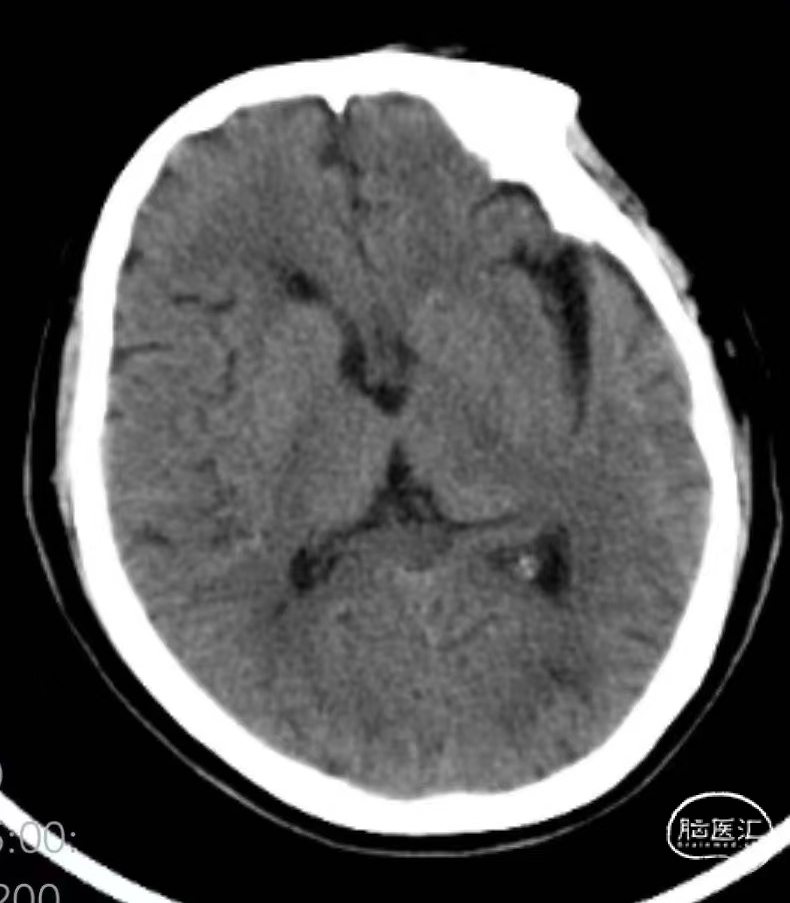

➤术后造影

➤术后CT

术后第二天复查头颅CT:无明显新发脑梗死。NIHSS评分7分(右上肢运动3分,右下肢运动2分,感觉1分,语言1分)。